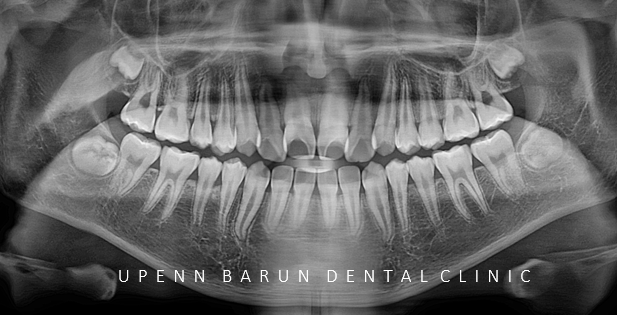

교정 진단을 위해 구내 사진을 찍어보았는데요

두번째 아래 앞니가 윗니를 덮고 있어 반대교합이 있을뿐만 아니라

앞니끼리 맞닿고 있어 치아가 마모되거나 치아끼리 힘을 받아 치은퇴축도 생길 수 있어

올바른 교합관계를 위해서 교정치료가 시급한 상황이었습니다.

이 학생의 경우 악궁이 좁아 웃을 때 덧니처럼 송곳니가 튀어나와 보이는 경향이 있었습니다.

일차적으로 악궁 확장 장치를 통해 치아 배열을 위한 공간 마련을 해주었습니다.

악궁확장을 통해 치아의 기능을 최대한 활용할 수 있도록 '발치 없이' 교정치료를 진행했습니다.